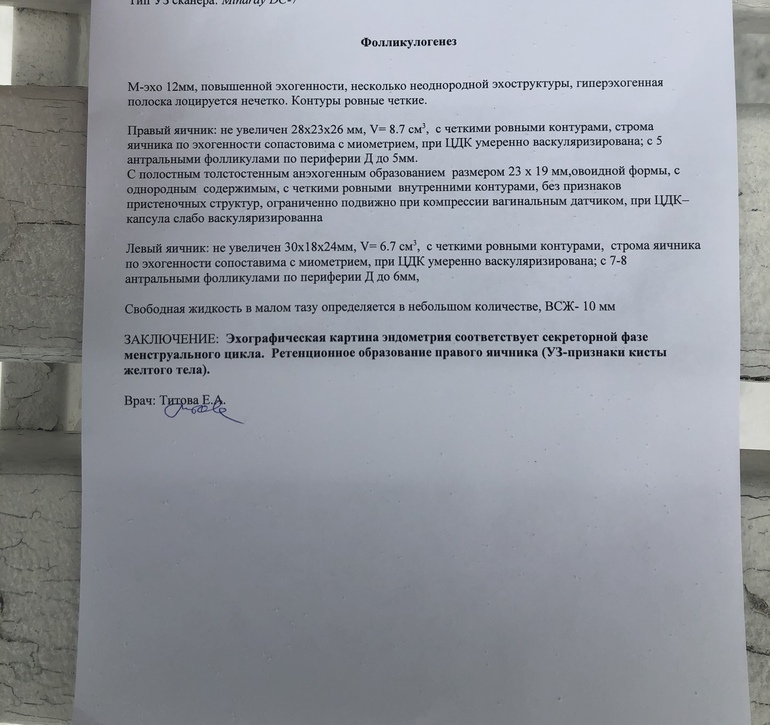

ФолликулометрияДевочки, привет!!! Сходила сегодня на узи (18 день цикла). Врач сказала, что овуляция была в правом яичнике! Но написала в заключении РЕТЕНЦИОННОЕ ОБРАЗОВАНИЕ размером 23мм x 19мм... То есть киста жёлтого тела. Пару циклов назад у меня была киста ЖТ, но она была почти 5 см!!!! А тут 23мм!!!

Я прочитала сейчас, что киста жёлтого тела это когда более 30 мм!!!!

Почему мне поставили кисту!!! Что скажете?!? Я очень расстроена! Отдала 1000 руб. теперь сижу в сомнениях. И это слово в заключении - ОБРАЗОВАНИЕ. Почему бы не написать ЖЕЛТОЕ ТЕЛО...но в скобках она указала -желтое тело кистозное.

У меня вопрос считается ли размер 23 мм кистозным жёлтым телом???

Киста или не киста зависит не от размера а от структуры. Киста заполненна жидкостью, а просто ЖТ как железа. Киста и меньшего размера может быть.

На УЗИ у кисты активный кровоток и зернистое включение. У Вас по картинке больше похоже на ЖТ, так как нет зерен. Но возможно именно по кровотока доктор определил что у Вас именно киста